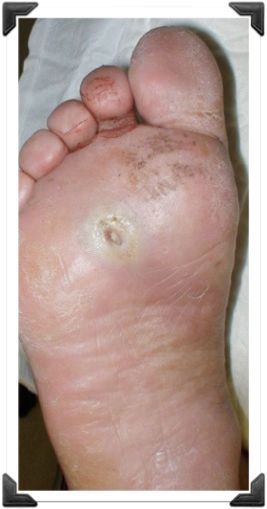

5 años Úlcera Plantar Recidivante

Dr. Luis Villanueva

Úlcera Neuropática 4to MT

Simple Osteotomía Percutánea